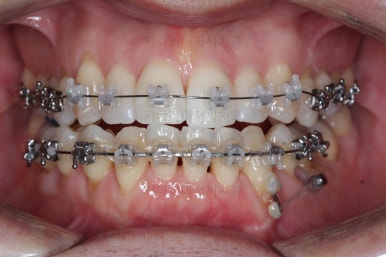

윗니도 장치를 부착했어요.

아랫니보다 해야 할 작업이 많지 않기 때문에 이렇게 시간차를 두어 진행을 했고, 이렇게 하면 교정장치가 눈에 띄는 기간이 줄어들어 환자분의 만족도는 더 올라가게 되죠.

아랫니 이 뽑은 자리는 거의 다 다물렸어요.

거꾸로 물리는 앞니도 어느 정도 많이 개선이 되었고요.

이 정도 진행되면 입매에 대해서 평가를 합니다.

외모도 좋아졌고 교합도 개선되어 가고 있기 때문에 좀 더 정교한 마무리를 하고 치료 종료하기로 했어요. 모자렀던 부분도 더 가지런하게 하고 있어요.

점점 마무리에 가까워지고 있습니다.